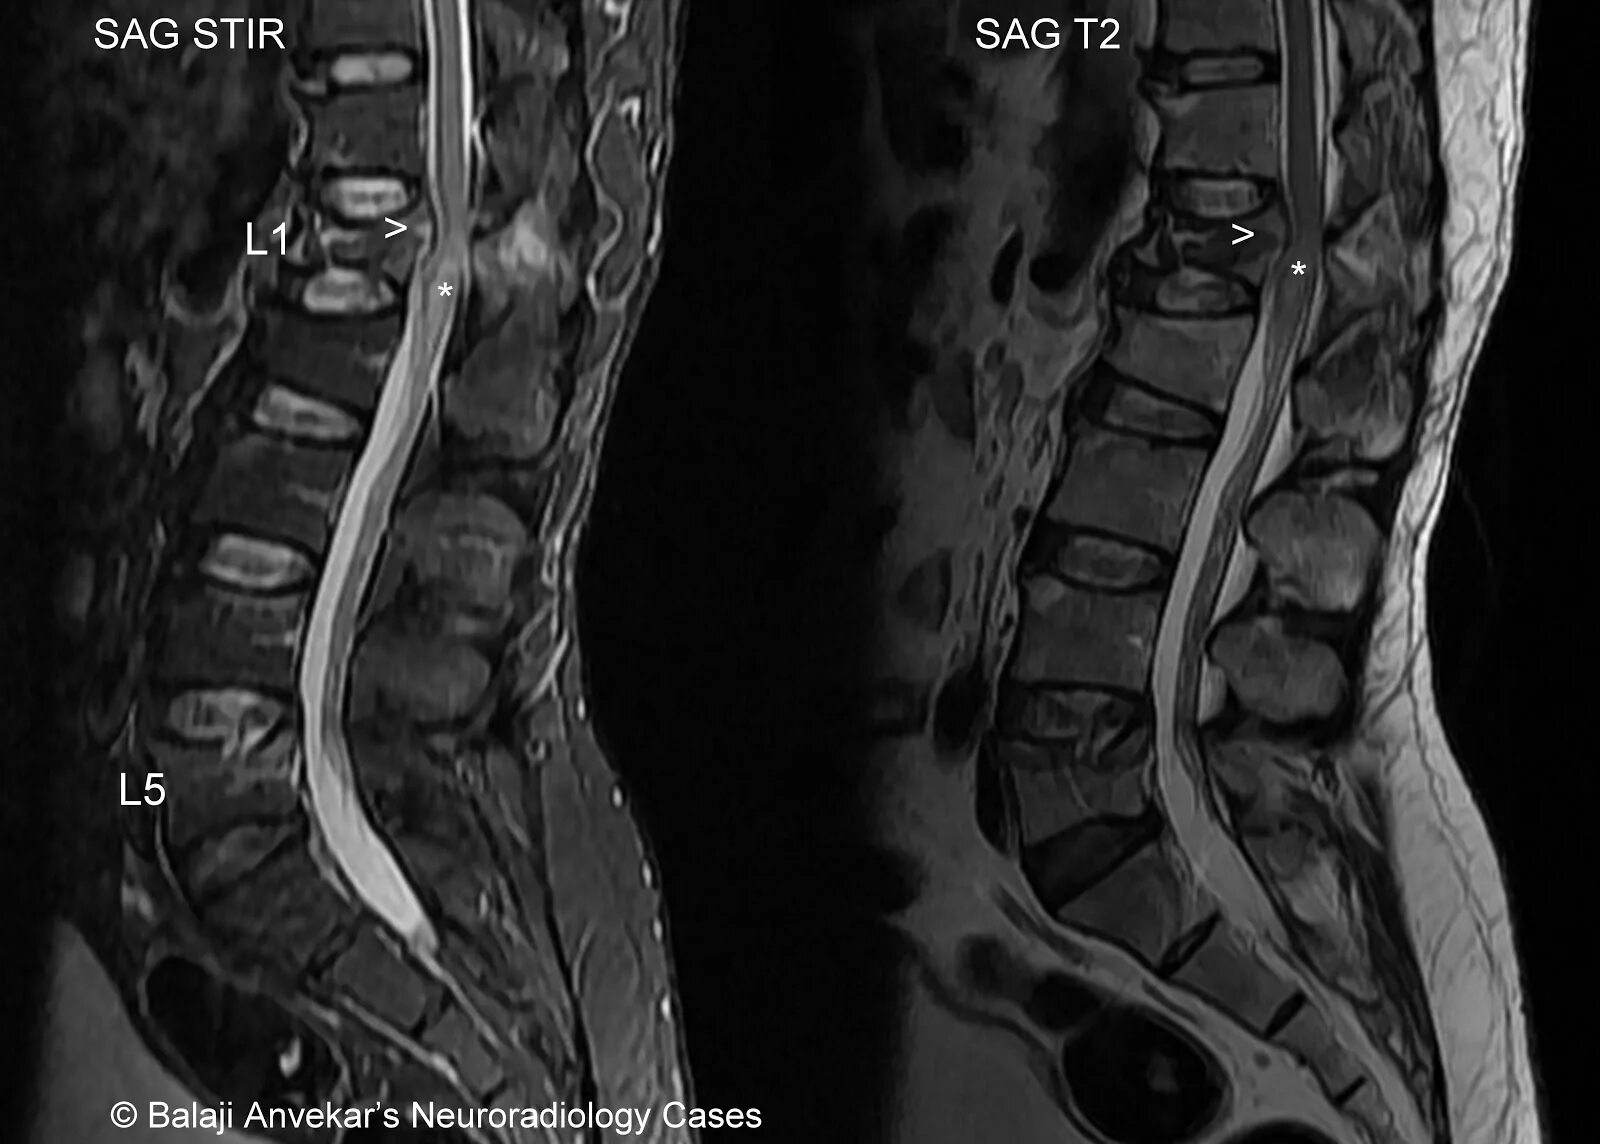

Spine mri